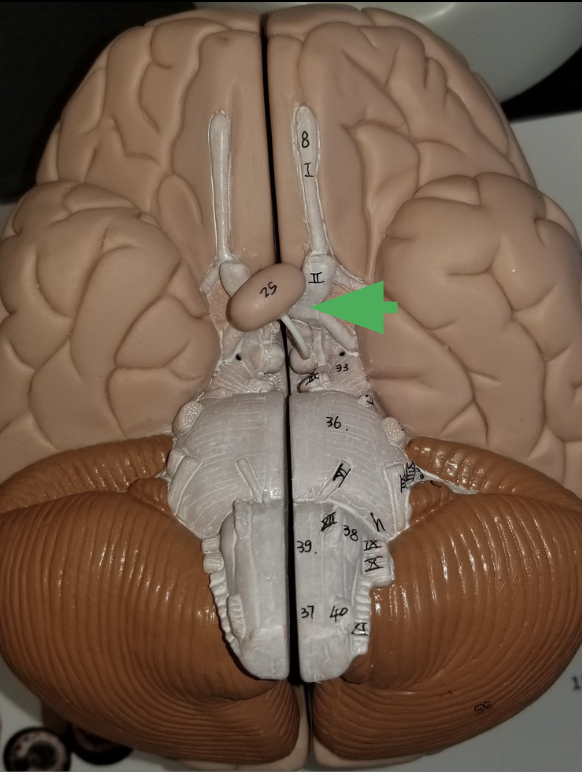

what does the arrow indicate ?

Optic chiasm

What happens in the optic chiasm?

where some axons in each optic nerve cross over to the other side